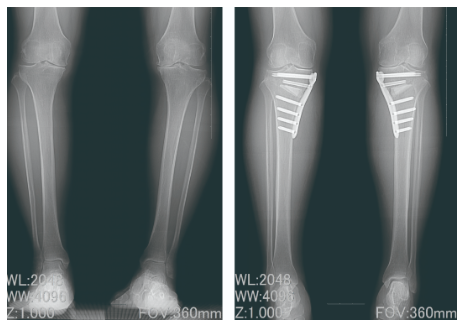

手術療法例-3 《高位脛骨骨切り術》

高位脛骨骨切り術(HTO手術)とは、脚の形をO脚からX脚に変える手術で、内側に曲がっている脚を、自分の骨を切って角度を変えることで、反対の外側に移動させます。骨が癒合するまで多少痛みがあったり、リハビリをしっかり行う必要がありますが、自分の関節を温存し、機能を維持することができるため、術後の日常生活の制限が比較的少なくなります。

正座がしやすかったり、スポーツや農業などの仕事へ復帰される方も多くいます。